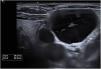

This is the case of a 66-year-old woman who presented to the dermatology office with a 6-month history of a lump on the left latero-cervical region without any accompanying symptoms. Her past medical story included thyroiditis and alfa-1 antitrypsin deficiency. The physical examination revealed the presence of a painless and non-inflamed 3cm nodule on the left latero-cervical region (Fig. 1). The neck ultrasound performed revealed the presence of a 3cm×2.1cm cyst with no peripheral or internal vascularity, which was consistent with a cyst (Fig. 2). The ultrasound-guided FNA and biochemical study of the content revealed the presence of elevated triglyceride levels (438mg/dL; normal range <150mg/dL), with normal cholesterol levels (82mg/dL; normal range <200mg/dL). To rule out any organic or treatable disease, a thoracic CAT scan was performed (Fig. 3).

CTDC often presents as a painless and asymptomatic cystic mass on left supraclavicular region. However, it can cause swelling, discomfort, vague neck pain, dyspnea, cough, mild dysphagia, palpitations, arm swelling and sore throat following the compression of proximal structures.1